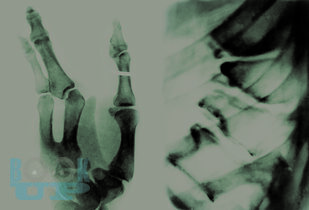

В монографии на примере опорно-двигательной системы рассмотрены различные врождённые, а также приобретённые в постнатальном периоде нарушения формирования (по-гречески – дисплазии) под воздействием разнообразных повреждающих факторов.

Изменения организма, приобретённые после окончательного его формирования, автор рассматривает не как возрастную норму, а как возрастную патологию, которой проявляется старение. Показано влияние внешних и внутренних факторов (механические перегрузки, экология, питание, заболевания внутренних органов, особенно эндокринной системы) на процессы непрерывной перестройки организма.